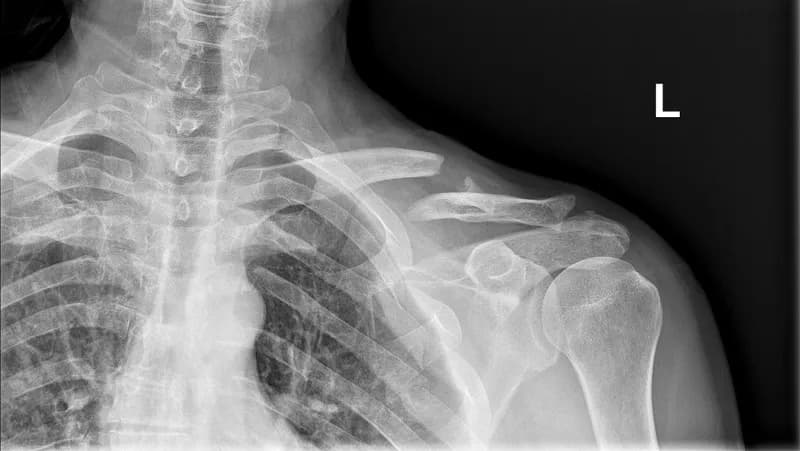

Rehabilitacja po złamaniu obojczyka różni się w zależności od rodzaju złamania. Istnieją trzy główne typy złamań obojczyka: złamania nieprzemieszczone, złamania przemieszczone oraz złamania złożone. Każdy z tych typów ma inny wpływ na czas rehabilitacji. Na przykład, złamania nieprzemieszczone zazwyczaj goją się szybciej, ponieważ kość pozostaje w swoim pierwotnym położeniu, co ułatwia proces gojenia.

Z kolei złamania przemieszczone wymagają często interwencji chirurgicznej, co wydłuża czas rehabilitacji. Po operacji pacjenci mogą potrzebować więcej czasu na powrót do pełnej sprawności. Złamania złożone, które mogą obejmować uszkodzenia sąsiednich tkanek, również wymagają dłuższego okresu rehabilitacji, ponieważ proces gojenia jest bardziej skomplikowany. Warto zrozumieć, że każdy przypadek jest inny, a czas rehabilitacji może się znacznie różnić w zależności od indywidualnych okoliczności.